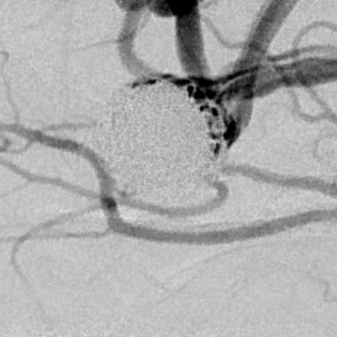

粗大分支从破裂瘤体上发出来,急性期能单纯致密栓塞吗?

病史:中年女性,新冠感染,颅内动脉瘤破裂,Hunt-Hess 4级

最终,动脉瘤瘤体致密栓塞,各个分支保留良好